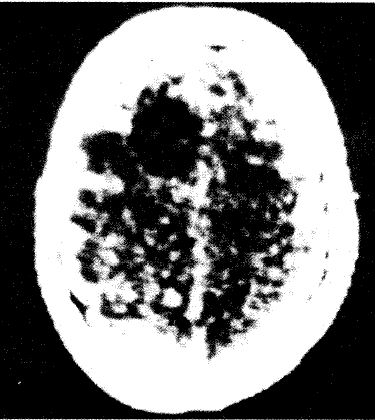

図13. CTの世代による画質の進歩.

いずれも前頭葉髄膜腫の症例.(左)1973年,第1世代CT(EMI)[4].(中)1980年,第2世代CT(EMI 1010)[5].(右) 1990年,第3世代CT (GE CT/T 8800)[5].着実な画質の進歩がわかる.